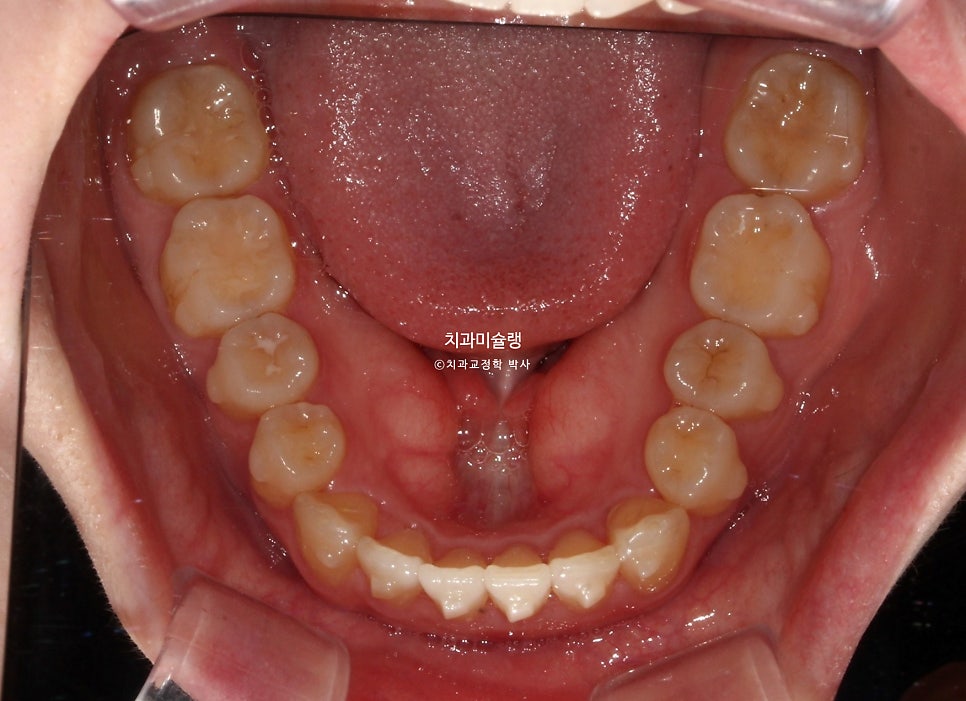

앞니뿐 아니라 어금니 교합관계가 2급입니다.

한쪽 사랑니가 깨끗하게 잘 나와있습니다. 반대쪽 사랑니도 곧 내려오겠죠.

교합은 물샐틈 없이 좋으며 사랑니까지 배열되었습니다.

사랑니까지 물샐틈 없는 교합을 보입니다.